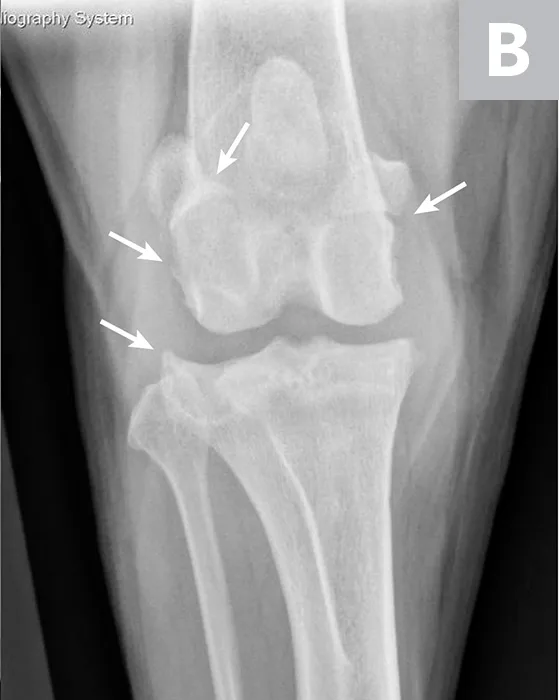

FIGURE 2

Mediolateral (A) and craniocaudal (B) radiograph projections of a 3-year-old spayed mastiff with right CCL rupture and medial meniscal tear. Osteophytes are present on the femoral condyles, patella, fabellae, and tibial plateau (arrows). There is increased soft tissue opacity in the joint space consistent with joint effusion (arrowhead). In addition, there is cranial displacement of the tibia relative to the femur on the lateral projection. These signs combined are consistent with CCL rupture.